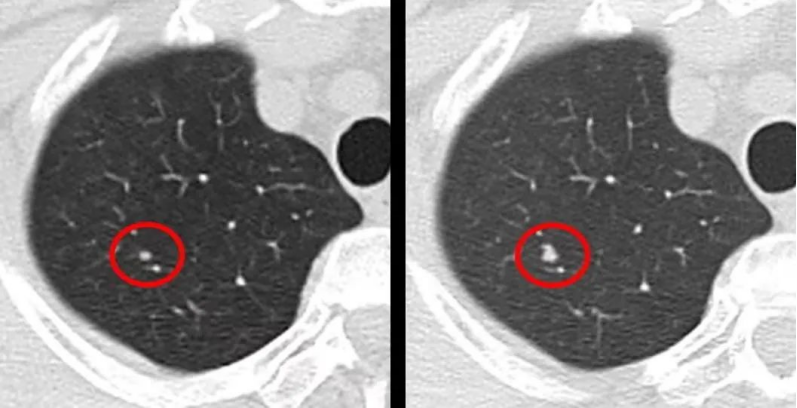

知己知彼,才能百战不殆,要想“盘”它,你需要知道一般小于5mm的微小实性结节,恶性概率极低,通常6-12月复查胸部CT。如果发现的是5-10mm的实性肺小结节,建议3-6个月复查,一旦露出恶性征象,就要及时切除,不影响预后。若是7-10mm的部分实性磨玻璃结节也可考虑短期抗感染治疗后复查,并咨询专科医生进一步处理。

3)胸部CT检查:一般发现一年内结节没有变化,继续随访观察即可,不用太担心。初期可以每三个月复查一次,若长期无变化,可逐渐延长至半年、九个月或一年一次。

对于大部分人来讲,10-30mm的结节,在咨询专科医师前提下,权衡利弊后没有什么禁忌的话,可考虑外科手术切除,因为这类病变的恶性概率相对较高,对于8mm以下,连续CT扫描进行随访变化不大的,这类病变的恶性概率低,而切除的技术难度大,可选择继续随访。